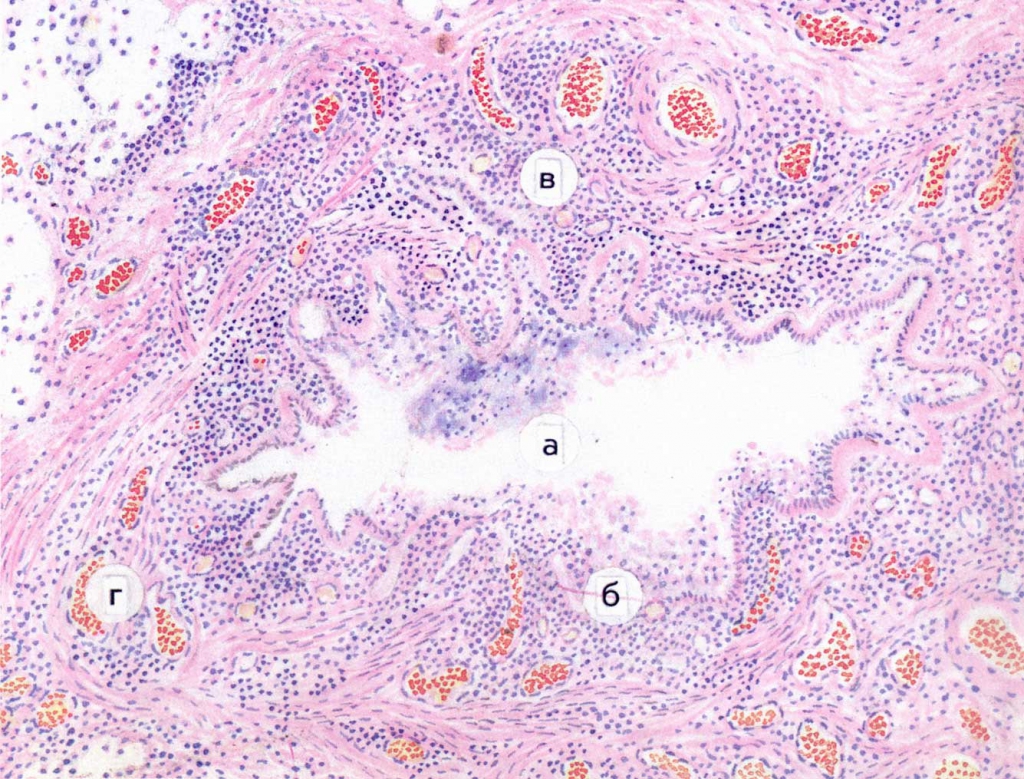

Карнификация Легкого: Микропрепараты и Диагностика

Раздел: Калейдоскоп образов